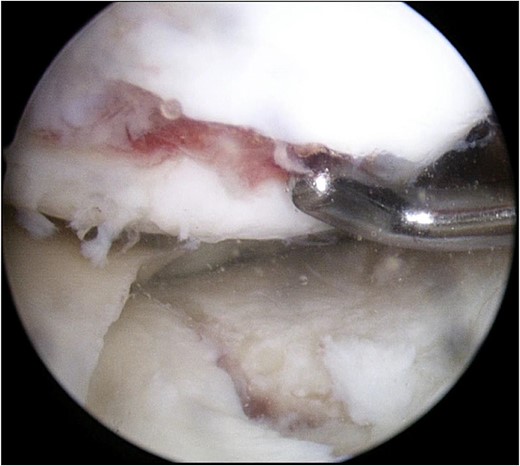

Postoperative MRI at 1 year after the surgery showed that the transplanted cultured cartilage had successfully integrated without any delamination (Fig. 6). A second-look arthroscopy was performed to evaluate the condition of the transplanted cartilage while removing the plate. The cartilage defect of the medial femoral condyle was covered by hyaline cartilage-like tissue. The depressed articular surface of the medial tibia plateau was smooth without stepping off (Fig. 7). One year after the surgery, the patient resumed daily life and sports activities without any complaint. The patient’s range of motion of the knee was full, and Lysholm’s knee score was 95.

Arthroscopic findings of the medial compartment of the left knee 1 year after the surgery. The cartilage defect of the medial femoral condyle was covered by hyaline cartilage-like tissue (A). The depressed articular surface of the medial tibia plateau was smooth without step-off (B).